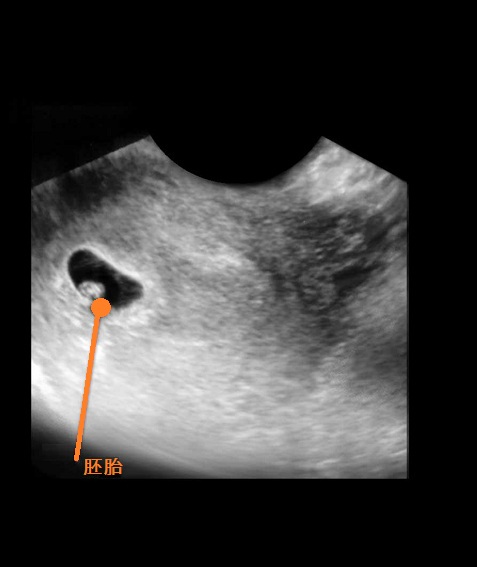

B超图

进入怀孕第6周后,在你的子宫里,胚胎正在迅速地成长,他(她)的心脏已经开始划分心室,并进行有规律的跳动及开始供血。这周的细胞还在迅速地分裂,主要器官包括初级的肾和心脏的雏形都已发育,神经管开始连接大脑和脊髓,原肠也开始发育。

胚胎的上面和下面开始长出肢体的幼芽,这是将来孩子的手臂和腿。日后将形成嘴巴的地方的下部,有一些小皱痕,它最终会发育成脖子和下颌。在本周面部的基本器官已经开始成形,已经能清晰地看到鼻孔,眼睛的雏形也已经具备。